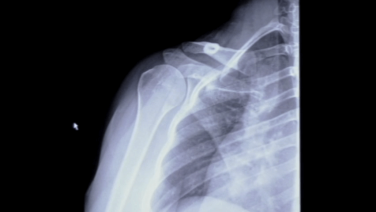

MRI & Xray Review Labral Tear Shoulder with Stephanie Muh, MD